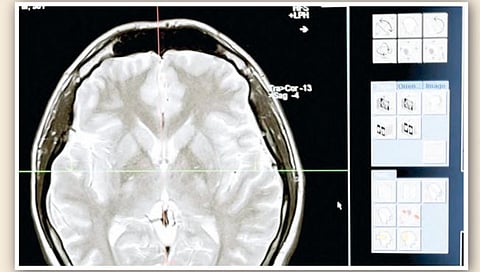

लंडन : जनरेशन झेड म्हणजे 1997-2012 दरम्यान जन्मलेले लोक आणि जनरेशन अल्फा म्हणजे त्यानंतर जन्मलेले लोक. अशा लोकांचा मेंदू 100 वर्षांपूर्वी जन्मलेल्या लोकांपेक्षा आकाराने मोठा आहे. 'डेली मेल' या ब्रिटिश वेबसाईटमध्ये प्रकाशित झालेल्या एका अभ्यासात असे दिसून आले आहे की, एकीकडे त्यांच्या मेंदूच्या आकारात वाढ झाली आहे, तर दुसरीकडे या दोन पिढ्यांचा 'आयक्यू' म्हणजेच बुद्ध्यांक मागील पिढ्यांच्या तुलनेत कमी झाला आहे. हा अभ्यास काय सांगतो ते जाणून घेऊया…

अभ्यासानुसार, विद्यापीठाच्या 'यूसी डेव्हिस हेल्थ रिसर्च'ने 1930-1970 मध्ये जन्मलेल्या लोकांच्या मेंदूच्या विविध आकारांवर एक अभ्यास केला. ज्यामध्ये हे समोर आले की, सायलेंट जनरेशन म्हणजे 1928-1946 दरम्यान जन्मलेले लोक. जनरेशन एक्स म्हणजे1965-1980 दरम्यान जन्मलेल्या लोकांच्या तुलनेत मेंदू 6.6 टक्क्यांनी वाढला आहे. हे अनेक सामाजिक, सांस्कृतिक आणि आरोग्याशी संबंधित पैलूंमुळे असू शकते, असे अभ्यासात म्हटले आहे. याशिवाय या लोकांमध्ये वयाशी संबंधित स्मृतिभ्रंशाचा धोकाही कमी होऊ शकतो.

या अभ्यासात असे म्हटले आहे की, तरुण पिढीच्या आयक्यू स्कोअरमध्ये लक्षणीय घट झाली आहे. ज्याचे कारण मोबाईल आणि इंटरनेटवरील वाढते अवलंबित्व आहे. शास्त्रज्ञांचे म्हणणे आहे की, एखाद्या व्यक्तीच्या मेंदूच्या आकाराचा त्याच्या बुद्धिमत्तेवर फारसा परिणाम होत नाही. दोन्हीमध्ये थोडा फरक आहे. एका मीडिया रिपोर्टस्नुसार, न्यूरोसायंटिस्टना असेही आढळून आले आहे की, मेंदूतील अतिरिक्त वजनाचा आपल्या बुद्धिमत्तेवर थोडासा प्रभाव पडतो. आपल्या मेंदूमध्ये अधिक स्मृती साठवण्यात मदत होऊ शकते. अभ्यासात असे दिसून आले आहे की, 1970 च्या दशकात जन्मलेल्या लोकांच्या मेंदूचा आकार 1930 मध्ये जन्मलेल्या लोकांच्या तुलनेत 6.6 टक्क्यांनी वाढला आहे.

75 वर्षांपासून केलेल्या या अभ्यासानुसार, आजच्या पिढीच्या मेंदूचा आकार सुमारे 1,400 मि.लि. आहे. त्याचवेळी, 1930 मध्ये जन्मलेल्या लोकांच्या मेंदूचा आकार 1,234 मि.लि. आहे. शिक्षण आणि आरोग्य क्षेत्रातील घडामोडींतूनच त्याची खरी कारणे शोधता येतील, असे संशोधकांचे म्हणणे आहे. 75 वर्षे केलेल्या या अभ्यासात असे आढळून आले की, 1970 मध्ये जन्मलेल्या लोकांच्या मेंदूचा आकार 1930 मध्ये जन्मलेल्या लोकांच्या तुलनेत 6.6 टक्क्यांनी वाढला आहे. संशोधनानुसार, आजच्या पिढीच्या मेंदूचा आकार अंदाजे 1,400 मि.लि., तर 1930 मध्ये जन्मलेल्या लोकांच्या मेंदूचा आकार 1,234 मि.लि. होता. एवढ्या वर्षांत असे का घडले, हे शिक्षण आणि आरोग्य क्षेत्रातील घडामोडींवरूनच कळू शकते, असे संशोधकांचे म्हणणे आहे.